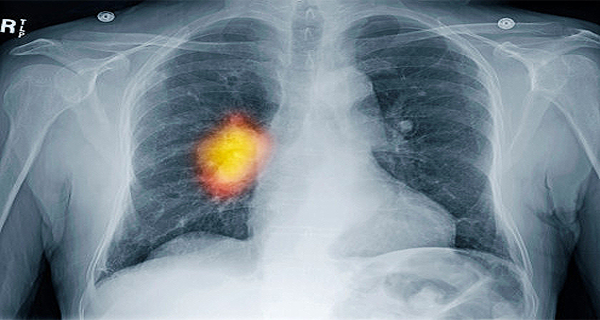

Old  Default Đây là dấu hiệu đầu tiên của bệnh UNG THƯ PHỔI!

Khi ung thư phổi được phát hiện sớm, nó có thể được chữa khỏi!

Ung thư phổi, được phát hiện ở giai đoạn đầu, là có thể chữa được tới 50%, còn với ung thư đã di căn, khả năng có thể chữa được chỉ khoảng 2%. Hãy chú ý đến những triệu chứng đầu tiên của bệnh ung thư phổi để tăng khả năng chữa bệnh cho mình...